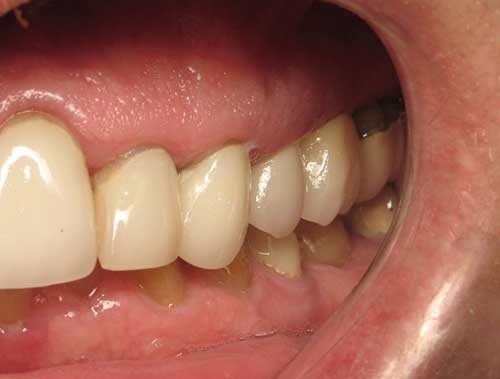

Peggy L.

This patient had broken her tooth and had an Implant placed to replace it.